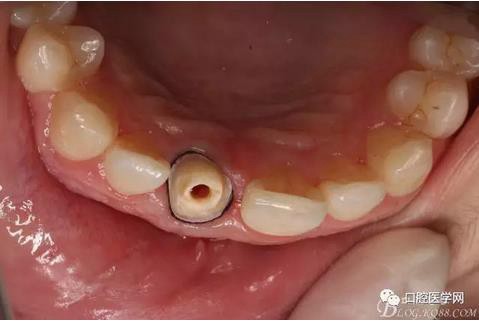

術(shù)前口內(nèi)照,11殘根,唇側(cè)牙齦紅腫,肩臺在齦下2毫米,舌側(cè)正常.21有被動萌出,長寬比例不協(xié)調(diào)。口腔衛(wèi)生一般,有菌斑。